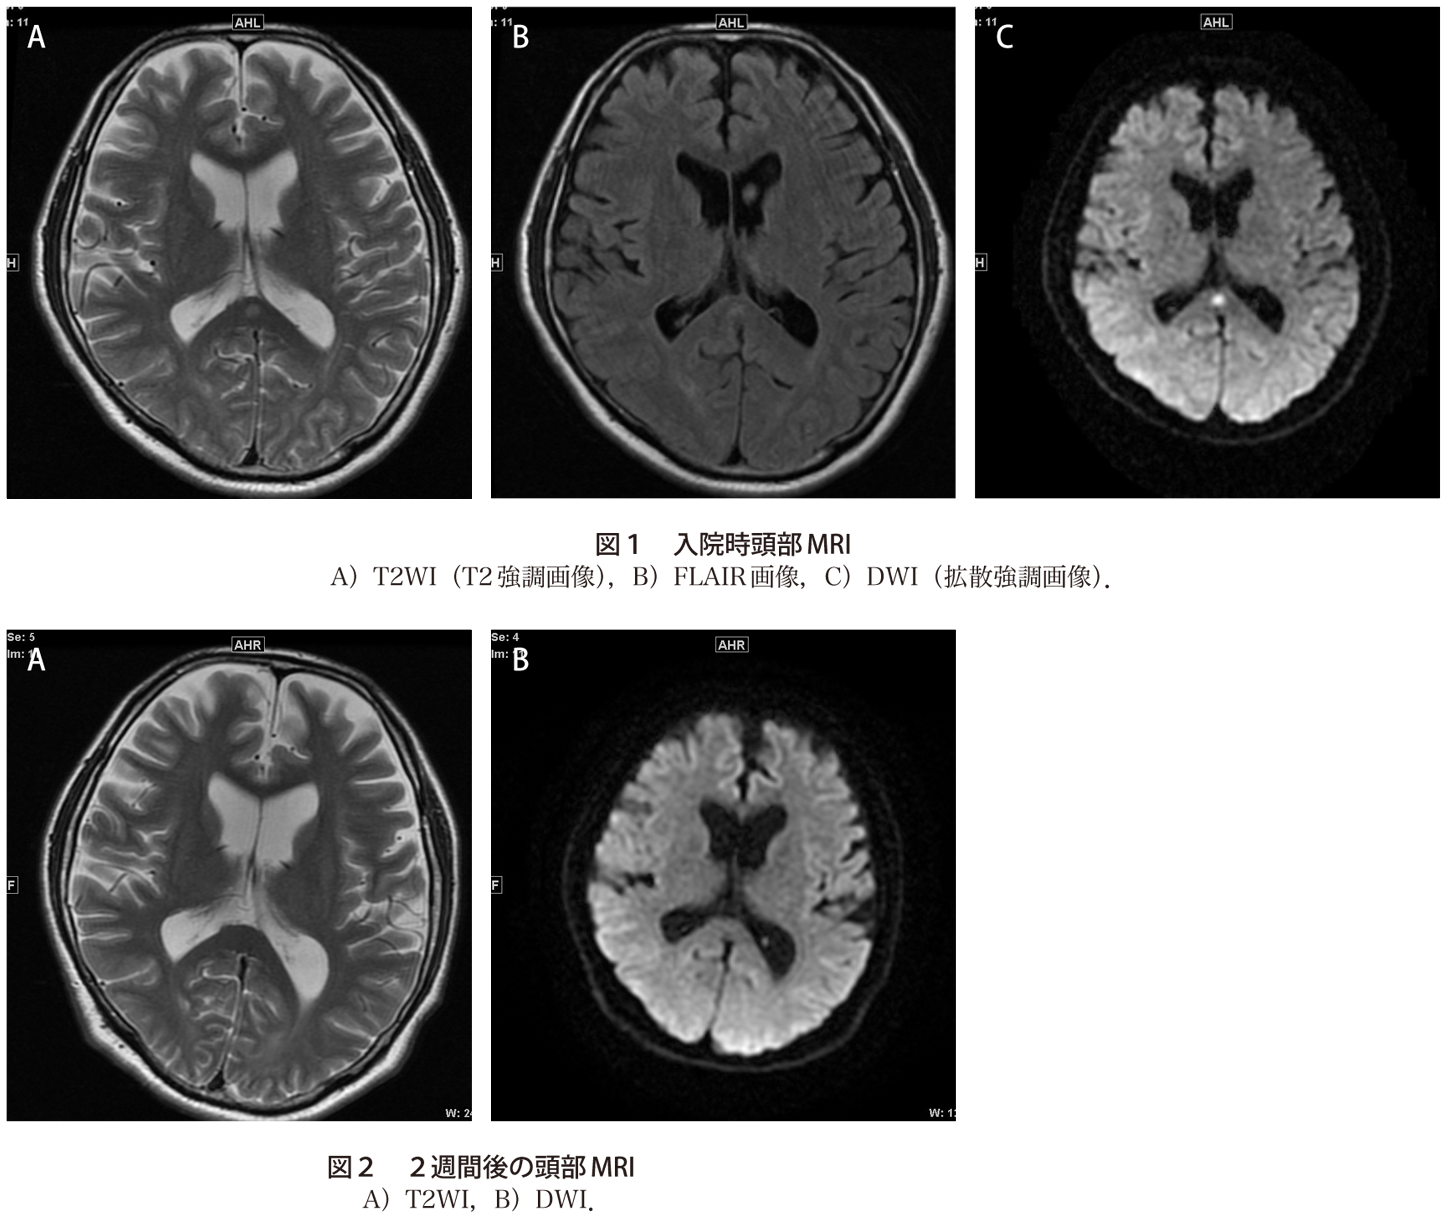

レジオネラ肺炎に伴う一過性の脳病変 実践 画像診断q A 羊土社 レジデントノート 羊土社